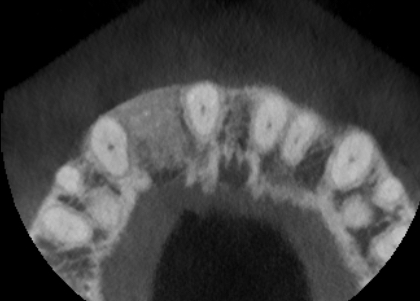

Healing was uneventful and following a seven-month maturation period, a CBCT scan confirmed the presence of the MinerOss®/autogenous bone graft and a favourable volume of bone. However, it was noted that the soft tissues covering the bone graft were thin with an absence of interdental papillae. It was determined that a connective tissue graft would be required as part of the next surgical procedure to improve the soft tissue volume and lead to the creation of papillae during the prosthetic stages.

Healing was uneventful and following a seven-month maturation period, a CBCT scan confirmed the presence of the MinerOss/autogenous bone graft and a favourable volume of bone.

The second surgery involved a palatal crestal incision and a full thickness flap elevation revealing good turnover of bone graft into host bone. A bone level implant was placed in an appropriate three-dimensional position completely surrounded by new bone and no additional bone grafting was required. A 4mm healing cap was placed.